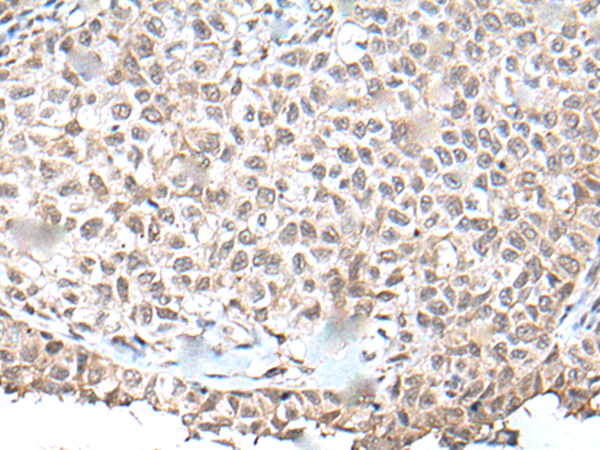

IHC positive control:

Human ovarian cancer and human tonsil